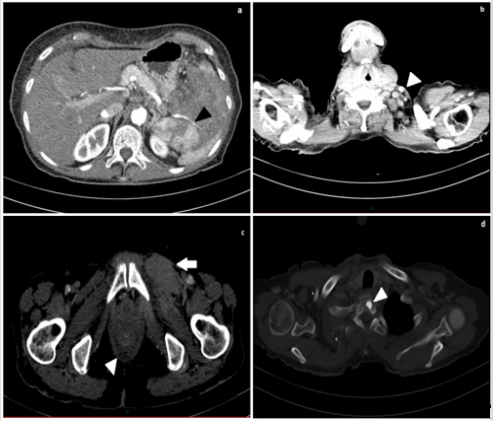

The patient performed a contrast-enhanced thoracic and abdominal computed tomography (CT), which showed enlarged lymph nodes (short axis of maximum 12 mm) at the left base of the neck, in both supraclavicular and retropectural regions, in celiac, paraortic, retrocaval and interaorto-caval areas. Enlarged lymph-nodes were also localized in the paratracheal site, in aortopulmonary window, in subcarinal and hilar area, bilaterally along the external iliac and common femoral vessels. In the left groin, some of them infiltrated ipsilateral internal obturator and adductor muscles, which appeared thickened and in homogeneously contrast enhanced. The spleen had a bipolar diameter of about 13 centimeters (cm), an inhomogeneous parenchymal structure due to the presence of newly formed solid tissue extending to the hilum close to the tail of the pancreas. Some enlarged lymph nodes were along the splenic vessels, which appeared narrowed and poorly contrast enhanced as per compression/infiltration. The liver appeared slightly enlarged but free from focal lesions of pathological significance and the bile ducts were not dilated. Mild effusion layers were in both pleural spaces, in the perihepatic space and in Douglas’ pouch. An osteoaddensing alteration of about 1 cm was in the soma of the first thoracic vertebra (D1) (Figure 2).

Figure 2:

a. Contrast-enhanced abdominal CT (arterial phase), showing inhomogeneous spleen parenchyma and narrowing of splenic vessels (black arrowhead);

b. Contrast-enhanced neck CT, showing enlarged later cervical lymph nodes (white arrowhead);

c. Contrast-enhanced CT of the pelvis: thickening of the left obturator muscle (white arrow) and mild effusion in the Douglas pouch (white arrowhead);

d. Contrast-enhanced CT: osteoaddensing lesion in the soma of the first thoracic vertebra D1 (white arrowhead).